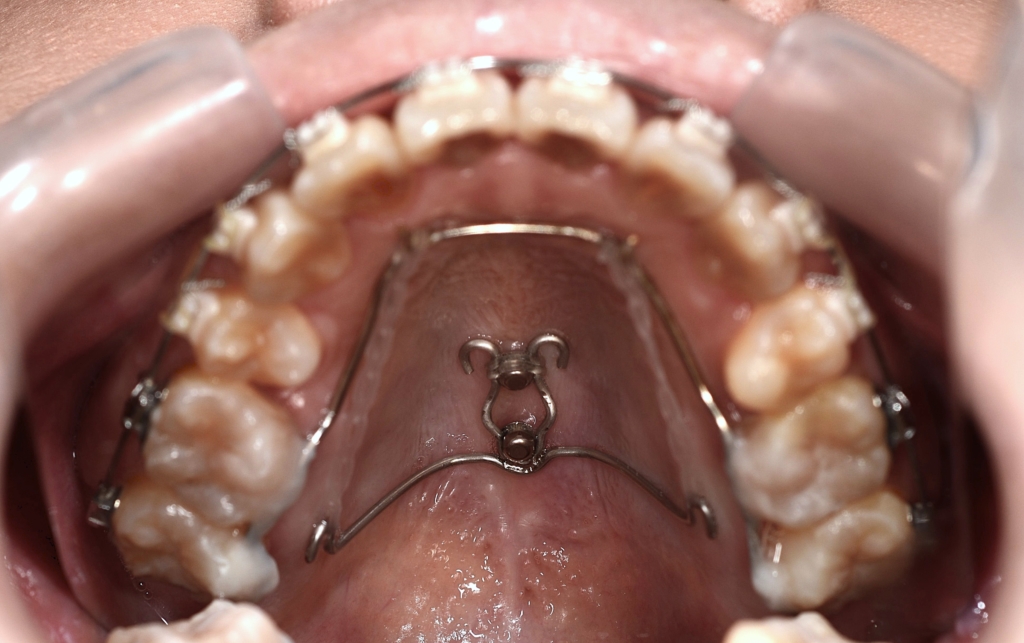

予定通り上顎の口蓋にアンカースクリューを植立しました。

あらためて上顎に、「PLAS」と「パラタルバー」を装着して、上の歯列全体を後方へ押して引っ込めて行きます。